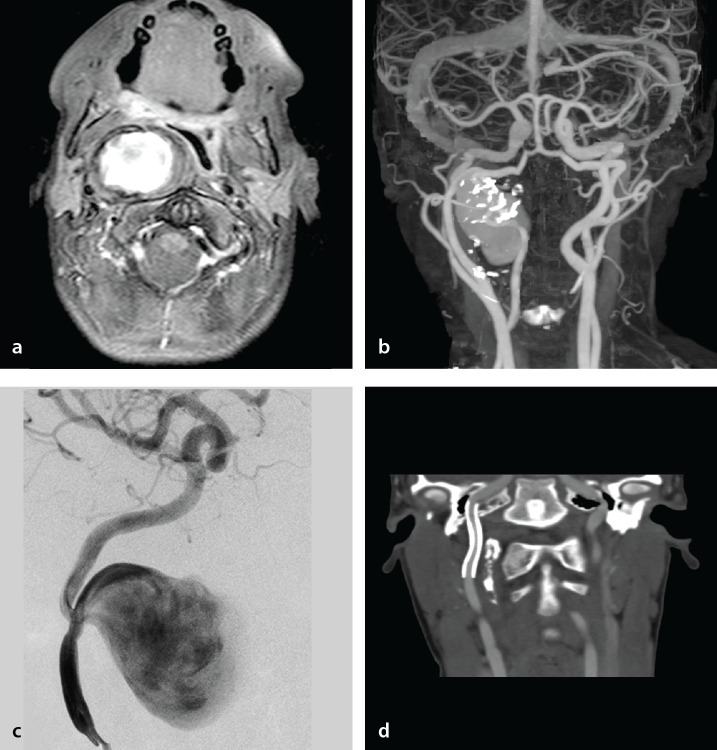

Abstract Image